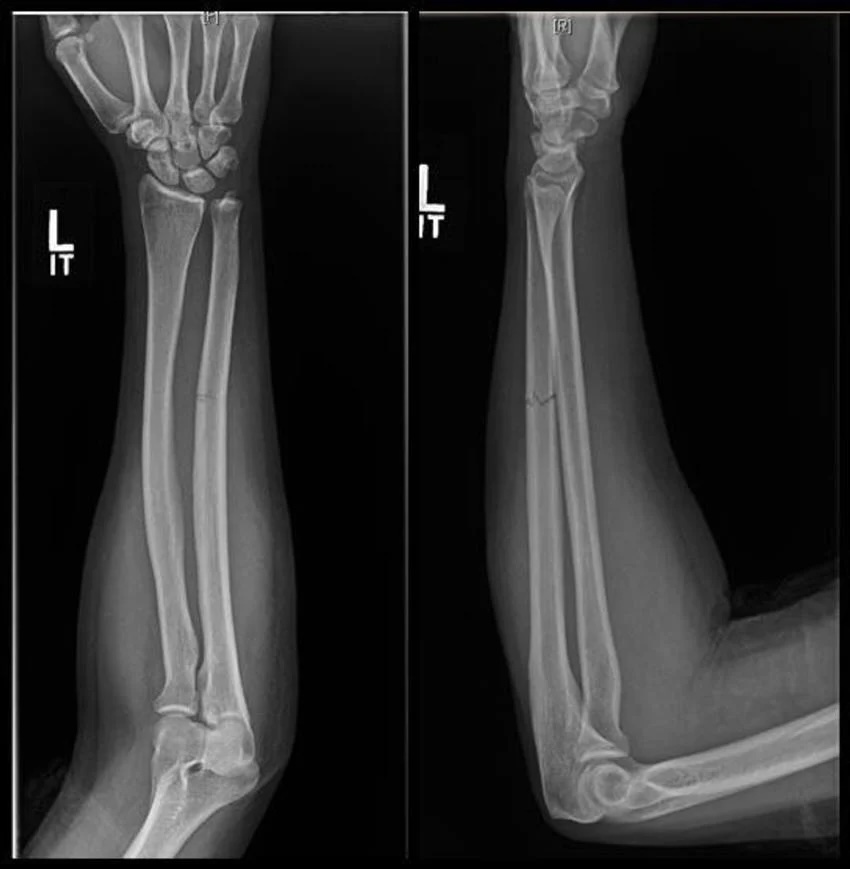

Переломы костей предплечья являются частым видом травмы опорно-двигательного аппарата. Предплечье состоит из двух длинных трубчатых костей — лучевой и локтевой. Эти кости участвуют как в стабилизации сустава, так и в обеспечении движений руки. Переломы могут быть изолированными (только одна кость) или сочетанными (обе кости), а также сопровождаться повреждением суставов, связок и нервов. Рентгенография предплечья в двух проекциях (прямая и боковая) является стандартом первичной диагностики и позволяет определить локализацию, тип перелома, наличие смещения и возможные осложнения.

Переломы диафиза (средней трети) лучевой или локтевой кости возникают при прямом ударе или падении на вытянутую руку. Перелом может быть поперечным, косым или оскольчатым. На рентгенограмме видна линия излома на уровне средней трети одной или обеих костей. Смещение отломков бывает значительным и часто требует оперативного вмешательства.

Одновременный перелом локтевой и лучевой костей — это тяжёлая травма, которая часто сопровождается деформацией, отёком и нарушением функции конечности. На рентгене видно два перелома на разных уровнях или в одной плоскости, и смещение отломков обычно выражено.

Исследование проводится в прямой (переднезадней) и боковой проекциях с применением прицельной съёмки повреждённого сегмента. Визуализируются прямые признаки (нарушение целостности кортикальной пластинки, линия перелома, фрагментация) и косвенные признаки (смещение оси, ангуляция, отёк мягких тканей). Цель обследования — точное определение локализации, характера и степени смещения перелома, выявление внутрисуставных повреждений и сопутствующих мягкотканных изменений.